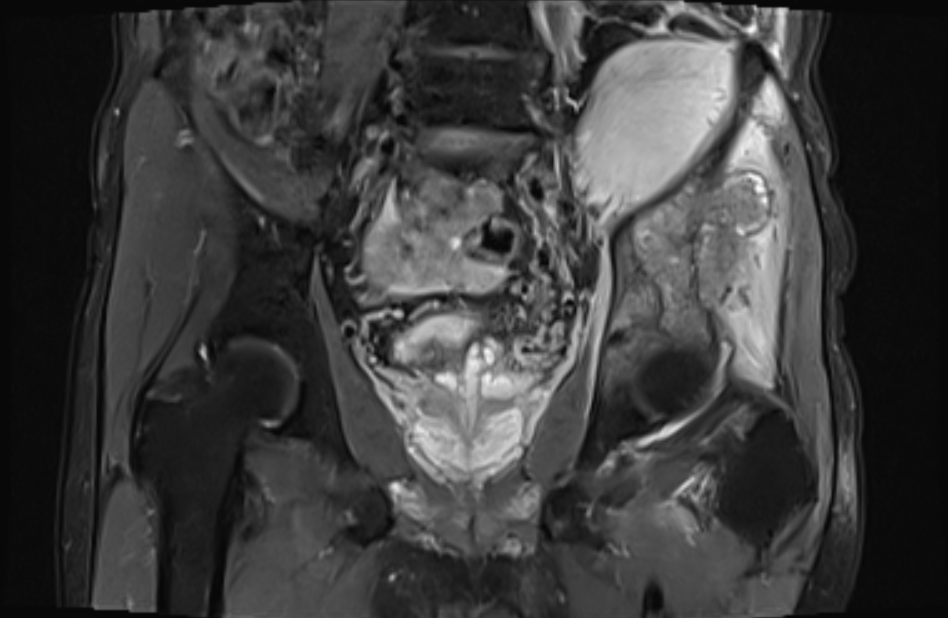

髋关节MR检查图像

MR表现:

左侧髂骨骨质破坏,累及髋臼,形成巨大软组织肿块,其最大径大致约 10.6cmx7.6cmx7.6cm;与邻近肌肉相比:T2WI肿块下部呈稍高信号,外 上部呈高信号,T1WI呈等高信号,其中可见斑点状高信号;DWI高b值, 肿块下部呈不规则高信号。瘤周肌肉可见水肿;左侧腰大肌前移。膀胱直肠窝可见少许液性信号影。

MR诊断:

1、左侧髂骨改变,结合病史,考虑转移瘤。

2、盆腔少许积液。